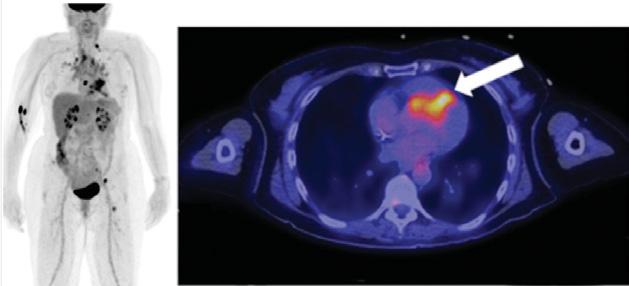

3. Évaluation de la sarcoïdose : il s’agit d’une maladie qui se caractérise par la formation anormale de tissu (granulomes) dans divers organes, dont le cœur (figure 1 ). Le recours à la TEP-FDG cardiaque dans les cas de sarcoïdose cardiaque est particulièrement important compte tenu du fait que le diagnostic de cette maladie peut être difficile. Les symptômes de la sarcoïdose cardiaque sont souvent vagues et peuvent être confondus avec ceux d’autres maladies comme l’insuffisance cardiaque ou la myocardite. En outre, les techniques d’imagerie traditionnelles, comme les échocardiogrammes et les IRM, peuvent ne pas être en mesure de détecter les premiers stades de cette maladie. Les granulomes observés dans les cas de sarcoïdose peuvent souvent être très inflammatoires, ce qui permet de les détecter à l’aide de la TEP-FDG cardiaque. Outre son utilité dans le cadre du diagnostic, la TEP-FDG cardiaque se révèle également utile pour guider le traitement chez la patientèle atteinte de la sarcoïdose. Le recours à la TEP-FDG cardiaque dans les cas de sarcoïdose cardiaque est une technique encore relativement nouvelle

Figure 1 : Exemple de TEP-FDG chez une personne atteinte de sarcoïdose cardiaque. Outre la détection de l’inflammation du myocarde, la TEP-FDG du corps entier permet de détecter les emplacements atteints à l’extérieur du cœur et d’obtenir davantage d’information sur le stade de la maladie.

Figure 2 : La TEP-FDG est un examen précis et simple pour l’évaluation de la vascularite. Chez cette personne atteinte d’une vascularite des gros vaisseaux, on observe un niveau élevé d’absorption dans la région de l’aorte abdominale.

zones d’activité accrue pouvant indiquer une inflammation. En comparant le niveau d’absorption du FDG dans les vaisseaux sanguins à celui d’un tissu sain normal, les médecins peuvent identifier les zones d’inflammation et évaluer l’étendue des dommages subis par les vaisseaux sanguins. La TEP-FDG peut également être utilisée pour surveiller l’évolution de la vascularite des gros vaisseaux ainsi que l’efficacité du traitement. L’examen peut aider à identifier une rechute précoce de la maladie et à évaluer la nécessité de modifier les plans de traitement. Dans l’ensemble, la TEP-FDG est un outil utile pour le diagnostic et la prise en charge de la vascularite des gros vaisseaux, car elle peut fournir des informations précieuses sur l’étendue et la gravité de l’inflammation dans les vaisseaux sanguins, ainsi que guider les décisions relatives au traitement et en surveiller l’efficacité.

5. Évaluation de l’endocardite : il s’agit d’une maladie qui se caractérise par une inflammation de la paroi interne du cœur, y compris les valves, en raison d’une infection (figure 3). L’infection peut entraîner la formation d’amas de bactéries et de cellules sanguines, appelés végétations, sur les valves cardiaques. Ces végétations peuvent endommager les valves et entraîner des complications comme une insuffisance cardiaque, un accident vasculaire cérébral et une septicémie. La TEP-FDG peut être utilisée pour détecter une infection des valves cardiaques, mais également pour surveiller l’évolution de l’endocardite ainsi que l’efficacité du traitement. L’examen peut aider à identifier une rechute précoce de la maladie et à évaluer la nécessité de modifier les plans de traitement.

Figure 3 : La TEP-FDG est particulièrement utile pour l’évaluation de l’endocardite sur prothèse valvulaire. Chez cette personne qui possède une prothèse de valve aortique, une zone importante d’absorption indique la présence d’une infection active.